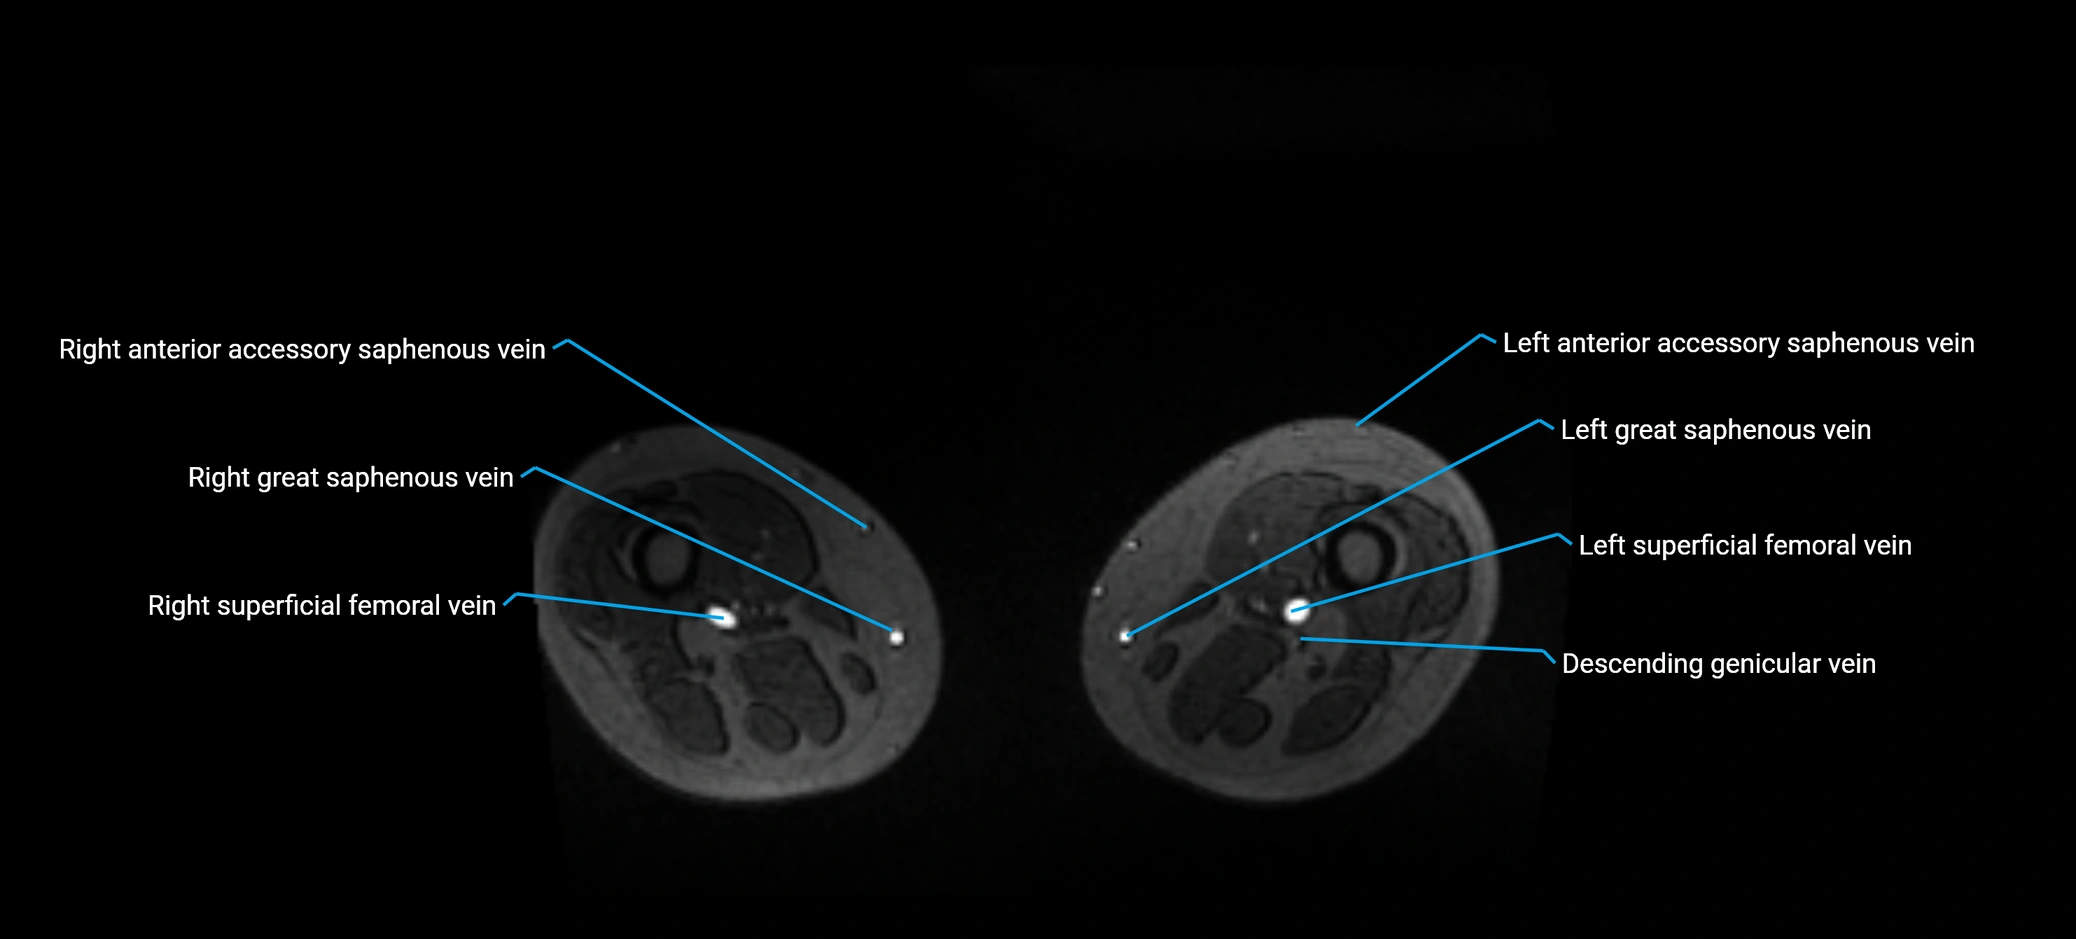

MRI image

image